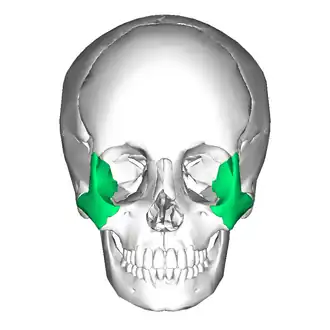

Eine laterale Mittelgesichtsfraktur oder Jochbeinfraktur ist ein Knochenbruch (Fraktur) der hauptsächlich das Jochbein (lateinisch Os zygomaticum) betrifft. An den lateralen Mittelgesichtsfrakturen können auch an das Jochbein angrenzende Knochenanteile beteiligt sein. Hierzu zählen der Processus zygomaticus des Schläfenbeins, der Processus frontalis des Stirnbeins, die gesamte laterale Wand der Augenhöhle (u. a. durch das Keilbein gebildet) sowie der kraniale Anteil des Oberkiefers. In der medizinischen Fachsprache wird eine laterale Mittelgesichtsfraktur auch als Fraktur des zygomatiko-orbitalen Komplexes bezeichnet.[1]

Die Frakturlinie verläuft meist entlang der Knochennaht (Sutur) zwischen Jochbein und Stirnbein (Sutura zygomatico-frontalis), der seitlichen Wand der knöchernen Augenhöhle (Orbita), entlang einer Knochenspalte im Boden der Orbita (Fissura orbitalis inferior), dem Foramen infraorbitale (Austrittspunkt des Nervus infraorbitalis aus dem Oberkiefer (Maxilla)), der oberen seitlichen und hinteren Wand der Kieferhöhle (Sinus maxillaris).